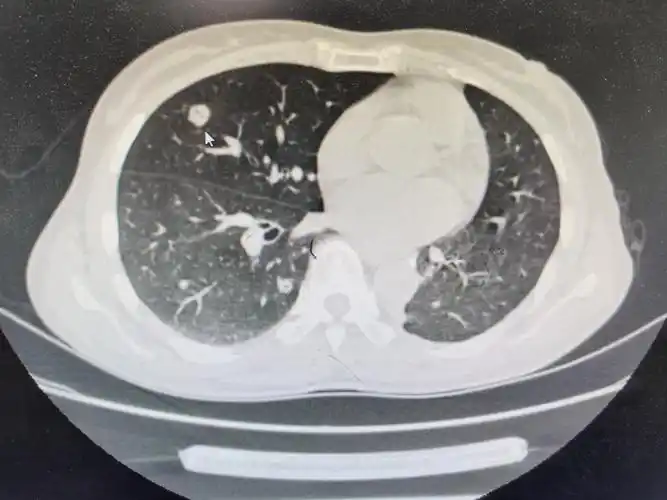

图文教你看懂恶性肺结节的ct表现

直径>20mm的恶性概率达到64%~82%肺结节按照密度,可以分为"磨玻璃

肺结节有明显的恶性成分就要考虑微创切除,等有症状才行动就晚了

查出肺结节,哪3种需要动手术?医生用ct片举例说明